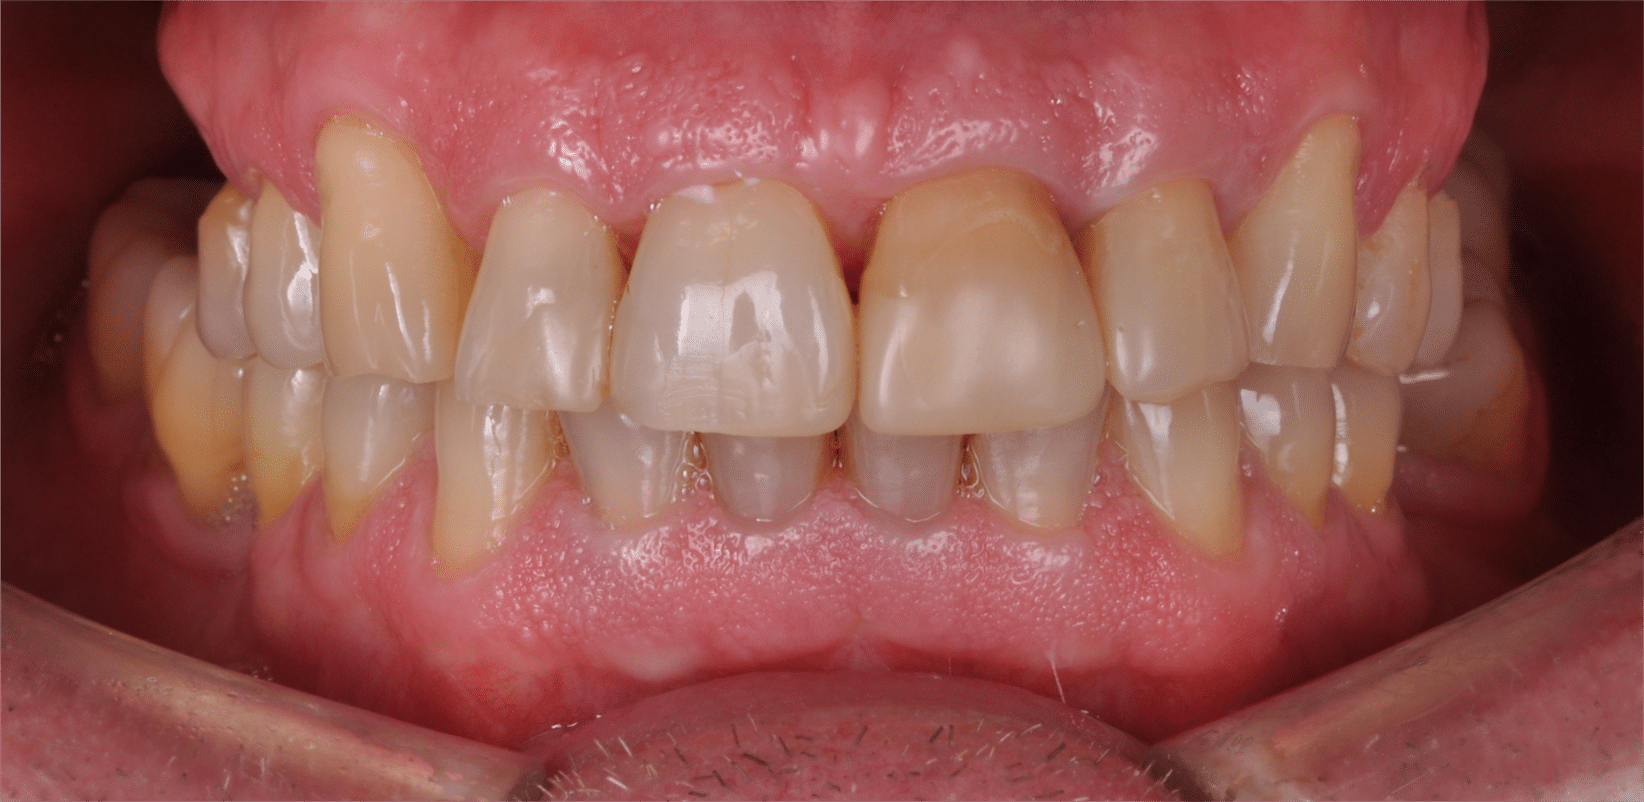

Doar astfel putem crea profilul de emergență corect al coroanei dentare, ceea ce permite conformarea papilei și a sulcusului.